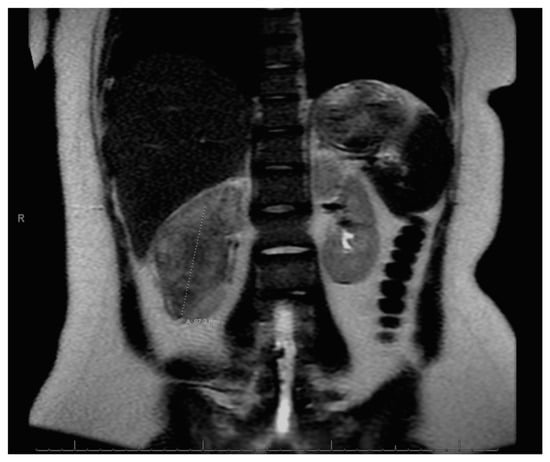

At age 15, she presented to an outside ER with a 2–3-day history of worsening right lower quadrant abdominal pain, nausea and occasional vomiting. She also had a history of a 20-lb weight loss over the past few months due to decreased appetite. CT scan showed a right renal mass 7 cm in size. She was transferred to our hospital and MRI abdomen/pelvis showed an indeterminate left adrenal nodule (Figure 3) and a large, solid, peripherally enhancing right renal mass with central heterogeneity measuring 8.1 × 5.4 × 8.7 cm (Figure 4). It also showed retroperitoneal lymphadenopathy with a retrocaval node at 4.1 × 2 cm, superior retrocaval node at 2.6 × 1.6 cm and an inferior precaval/aortocaval node at 1.5 × 0.9 cm. There was also a right lung nodule noted on a chest CT (Figure 5). She then had a baseline positive emission tomography (PET) scan which again showed the right renal mass, concerning for primary renal cell carcinoma, FDG avid retroperitoneal lymphadenopathy, concerning for metastasis and small bilateral pulmonary nodules, concerning for metastasis. She underwent a biopsy of the right renal mass, which was inconclusive. She underwent a second biopsy and was found to have RCCU-MP manifesting as a high-grade malignancy with loss of SMARCB1 by immunohistochemistry in the absence of a sickle hemoglobinopathy.

Figure 3. Left adrenal nodule.